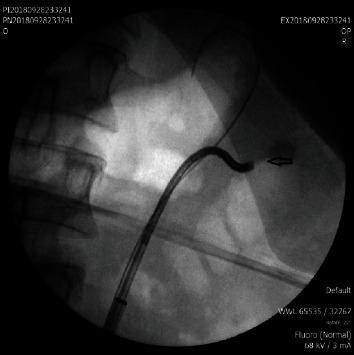

Actual Management of Anterior Calyceal Diverticular Calculi: A Challenging Flexible Retrograde Endoscopic Approach.

Calyceal diverticula is a cavity that communicates with the collecting system through a narrow isthmus of the kidney. The incidence of the formation of stones in calyceal diverticula is 10-50%. This paper reports three cases of two females and one male who presented with calyceal diverticular calculi; the patients have been, arbitrarily, selected between August and February 2019 at the urology department of our university hospital. A minimally invasive treatment includes extracorporeal lithotripsy (ESWL), and F-URS (flexible ureteroscopy) was performed. We report this case series.